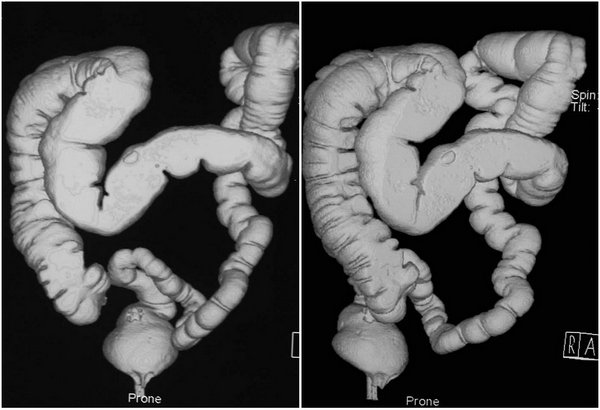

结肠CT充气造影技术:为大肠疾病提供了一种新的无创检查方法。结肠CT即利用CT采集结肠原始数据,在工作站使用计算机对其进行后处理,重建形成2D、3D图像,从而发现和诊断结肠病变。结肠CT成像已被证明与结肠镜检查的敏感性和特征性相当,被普遍作为一种预防、筛选结肠癌的经济有效的检查。

SSD(Surface Shaded Display,表面阴影显示)

VRT(Volume Rendering Technology,容积再现技术)